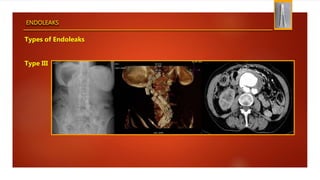

Types of Endoleaks

Type III

ENDOLEAKS